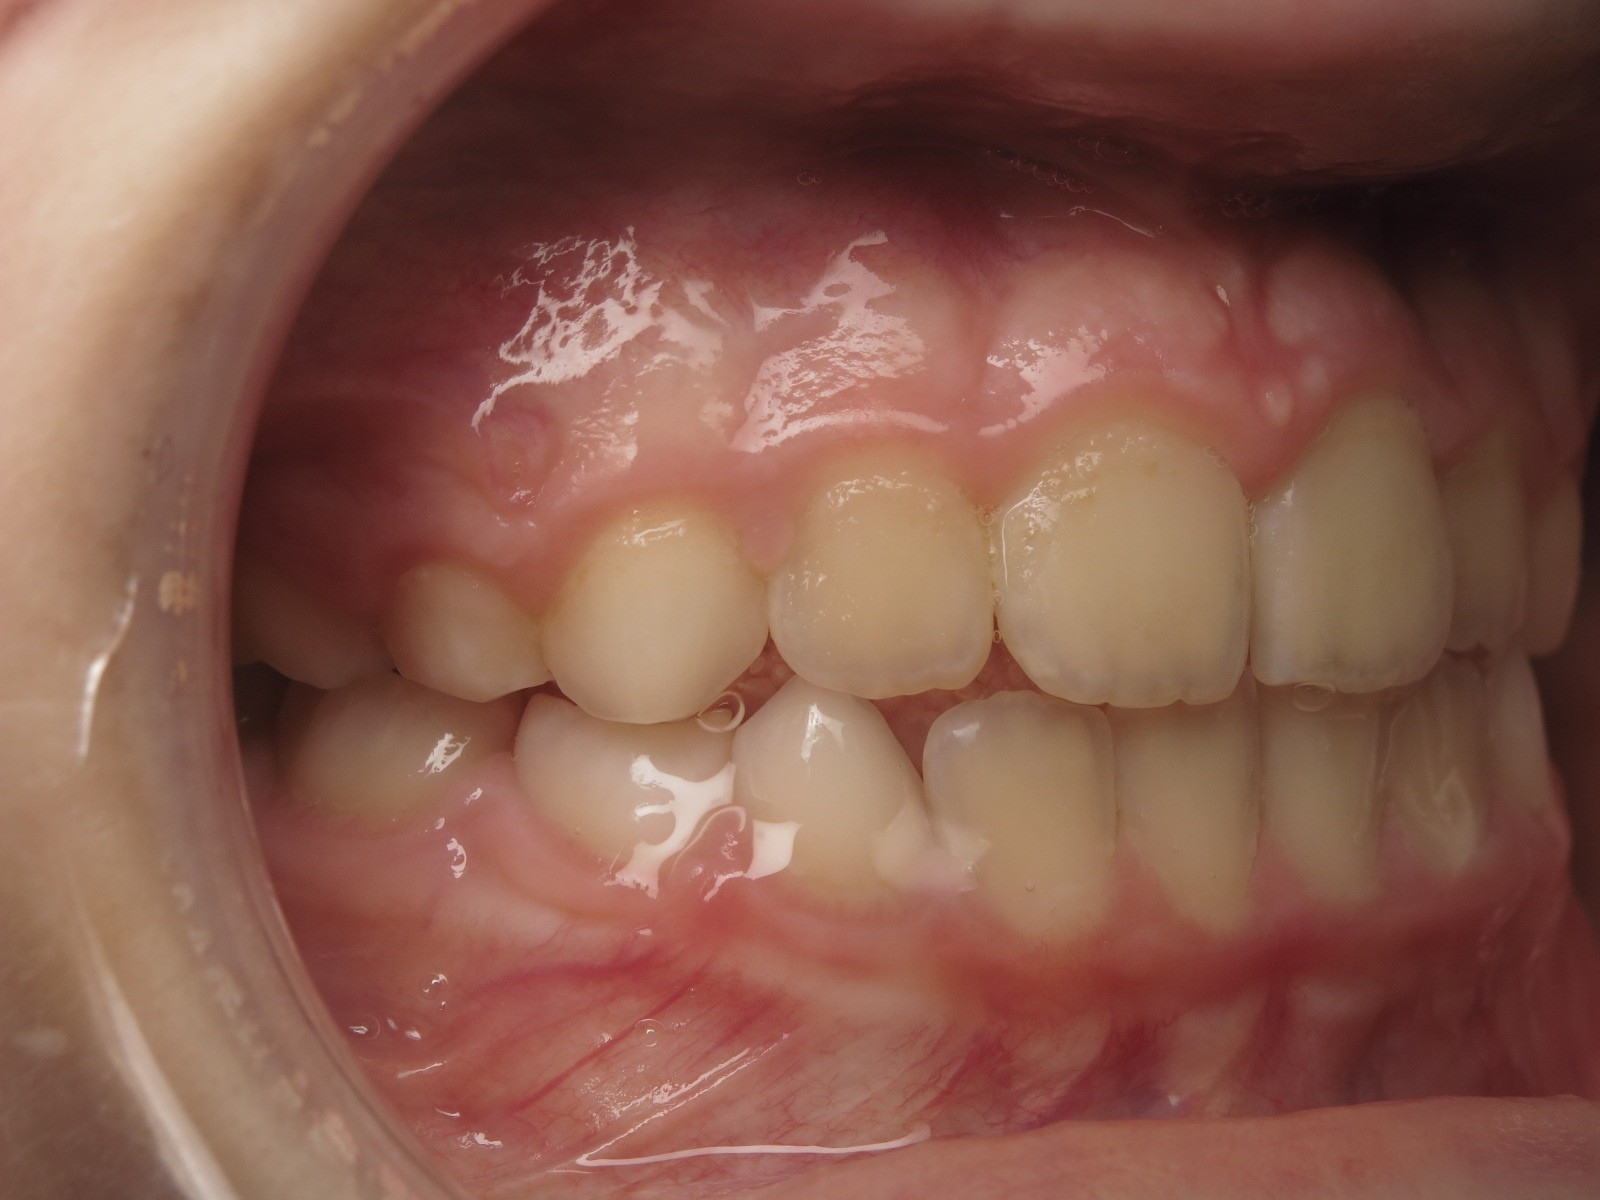

inversion des dents postérieur et espace entre l'arcade du haut et du bas (béance)

appareillage mobile pendant 3 ans

bilan de début et en cours de traitement